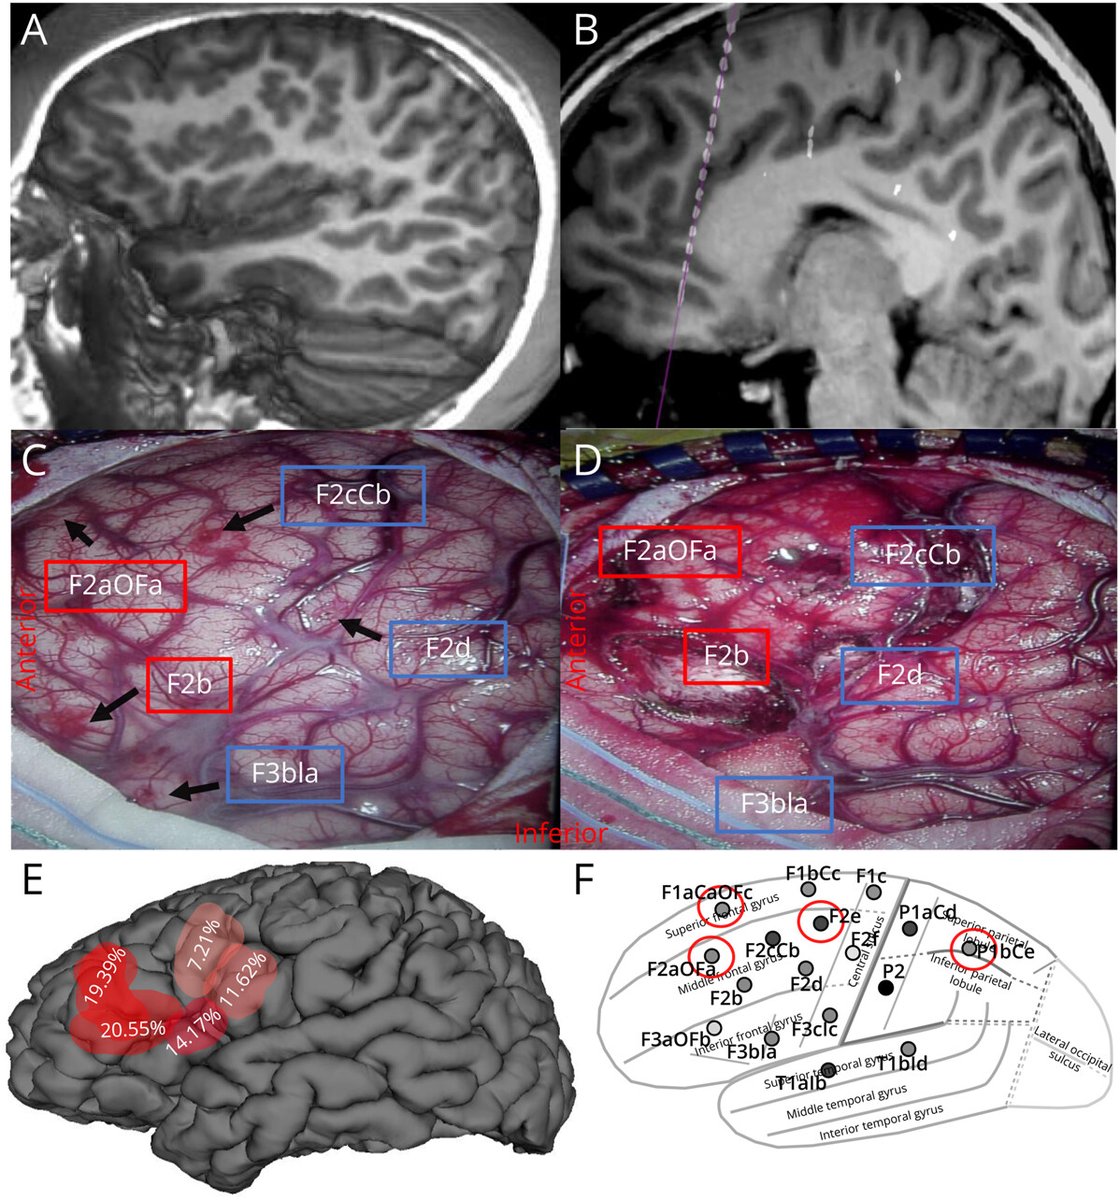

Continuing #EpilepsyAwarenessMonth we focus on a study from Dr. Westley Phillips and the @PRIME_Lab that looks at the correlation between the electrophysiologic and genetic signatures of epilepsy. It was found that regions with higher mutation burden were more epileptogenic.